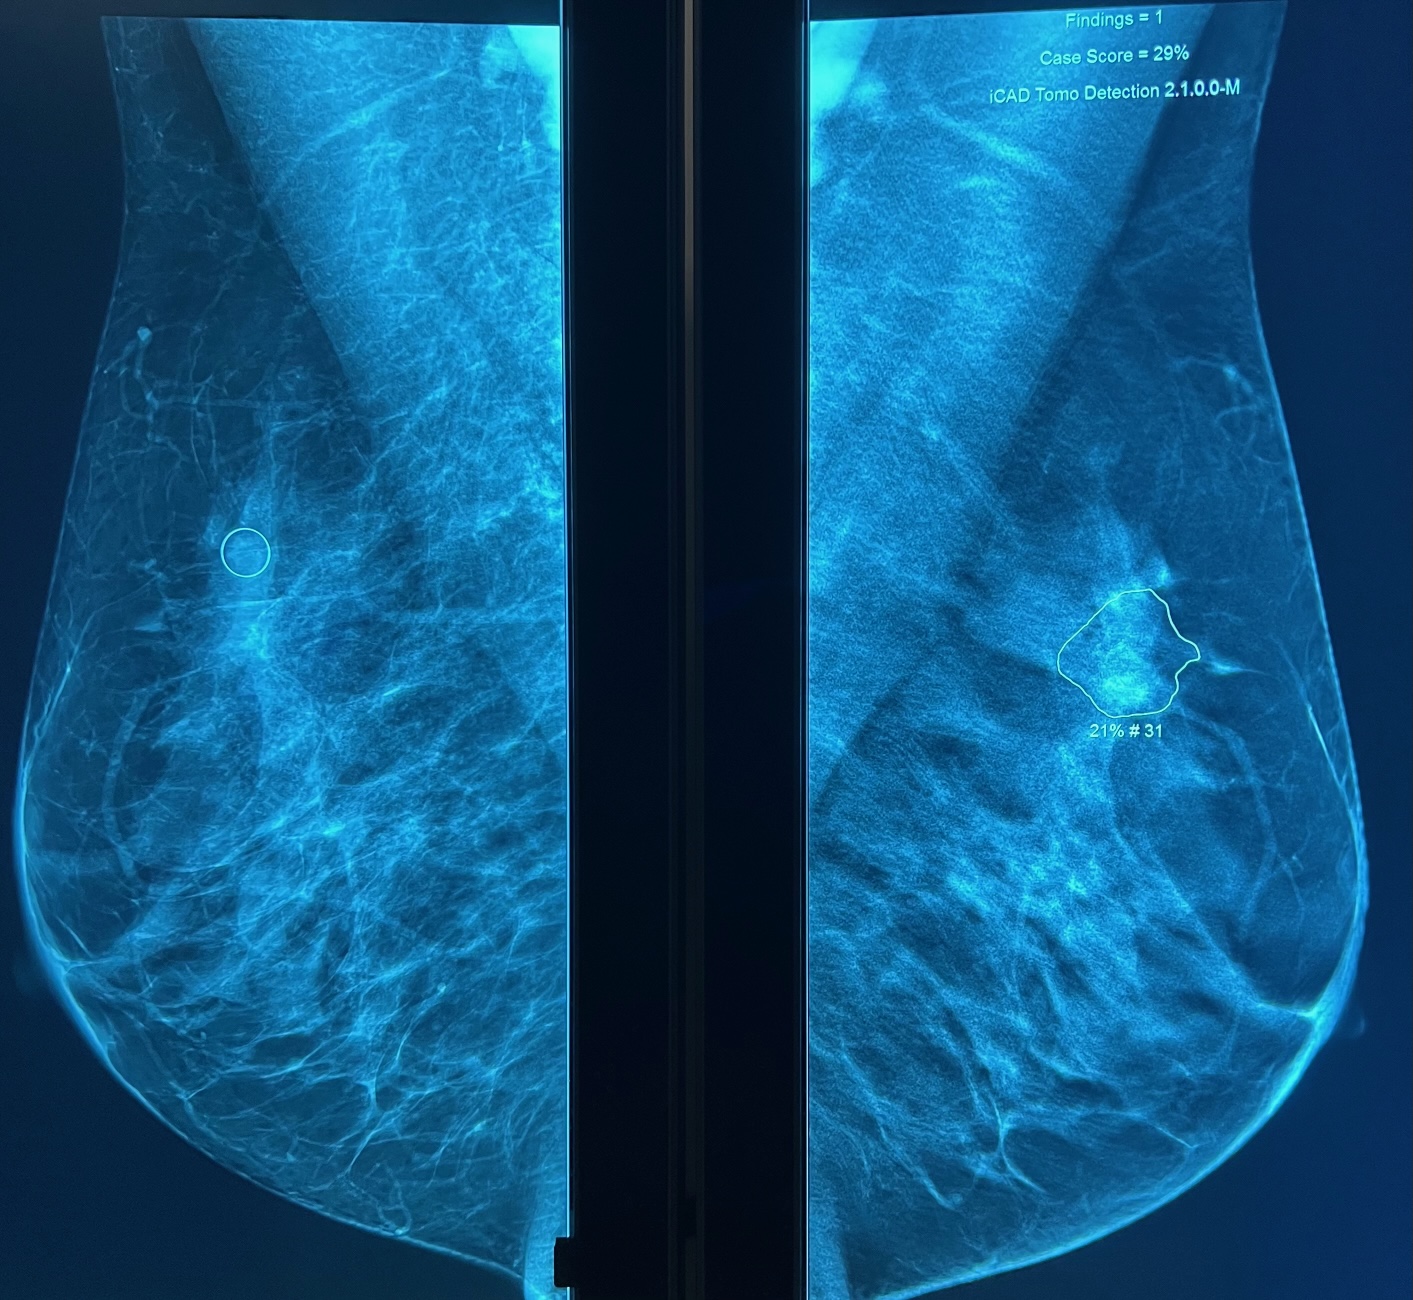

Le radiologue lit votre mammographie et dans un second temps utilise sur le mammographie numérique un CAD (computed aided detection), de dernière génération (ICAD pour imagerie 2D et tomosynthèse 3D) qui va marquer les micro-calcifications (marquées par un carré) et les masses (marquées par un rond) avec la valeur prédictive positve en faveur d'une lésion maligne.

Micro-calcifications (carré) Petite masse, distorsion architecturale (rond)

Valeur prédictive de lésion maligne 21%